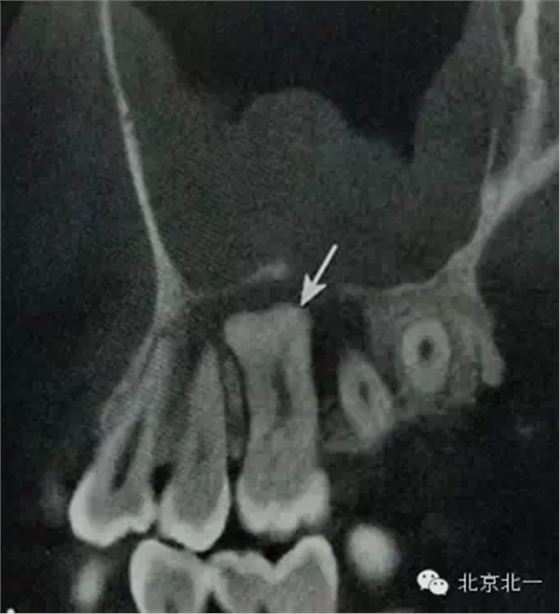

【CBCT表現(xiàn)】:

牙骨質(zhì)增生可表現(xiàn)為整個牙根體積的膨大,或僅表現(xiàn)為根尖呈球狀增生,對于多根牙,體積的膨大可局限于個別牙根,不伴根尖周感染的情況下,便便牙牙周膜及硬骨板影像相連續(xù)、完整。部分病例可見牙周膜間隙消失,牙根與牙槽骨粘連,導(dǎo)致牙齒萌出障礙或者滯留。

B6腭根根尖區(qū)膨大,牙周膜和骨硬板消失,根尖周見低密度影,上頜竇下壁骨質(zhì)不連續(xù),B B6頜面已開髓。